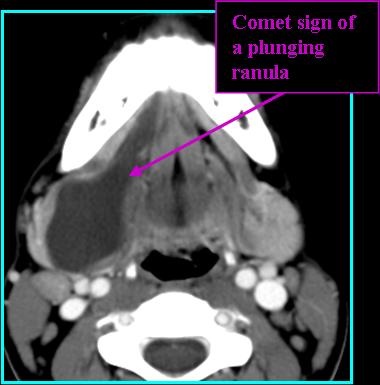

Radiologic Findings

- Plunging/diving ranulas show "tail sign": communication between collapsed sublingual and submandibular space (comet-shaped) (Liman et al. 2021)

- On CT: low-density, unilocular lesion, subtle ring enhancement, florid enhancement if infected